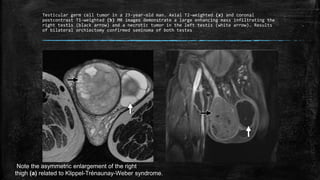

Testicular germ cell tumor in a 23-year-old man. Axial T2-weighted (a) and coronal

postcontrast T1-weighted (b) MR images demonstrate a large enhancing mass infiltrating the

right testis (black arrow) and a necrotic tumor in the left testis (white arrow). Results

of bilateral orchiectomy confirmed seminoma of both testes

Note the asymmetric enlargement of the right

thigh (a) related to Klippel-Trénaunay-Weber syndrome.

Testicular germ celltumor in a 23-year-old man. Axial T2-weighted (a) and coronal postcontrast T1-weighted (b) MR images demonstrate a large enhancing mass infiltrating the right testis (black arrow) and a necrotic tumor in the left testis (white arrow). Results of bilateral orchiectomy confirmed seminoma of both testes Note the asymmetric enlargement of the right thigh (a) related to Klippel-Trénaunay-Weber syndrome.